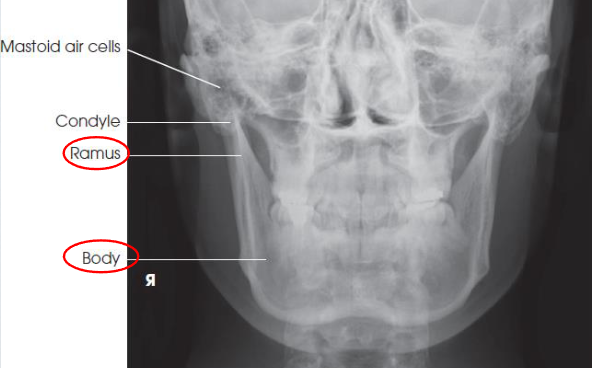

PA mandibular rami

patient position:

prone or upright

part position:

forehead and nose resting on IR

OML perpendicular to IR

MSP perpendicular to Ir

respiration suspended

CR:

perpendicular, exits acanthion

collimation:

1 inch beytond the lateral sides, above the TMJs, and below the chin

PA mandibular rami image criteria

mandibular body and rami

central part of body not well shown due to superimposition

shows medial or lateral displacement of fragments in fractures of the rami

no rotation or tilt:

symmetric mandibular body and rami

MSP of head aligned with long axis of collimated field

PA axial mandibular rami

patient position:

prone or upright

part position:

forehead and nose resting on Bucky/table

OML perpendicular to IR

MSP perpendicular to IR

respiration suspended

CR:

20-25 degrees cephalad, exits acanthion

collimation:

1 inch beyond the lateral sides, above the TMJs, and below the chin

PA axial mandibular rami image criteria

mandibular body and rami

central part of body not well shown due to superimposed spine

demonstrates medial or lateral displace ment of fragments in fractures of the rami

no rotation or tilt:

symmetric mandibular body and rami

MSP of head aligned with long axis of collimated field

condylar processes